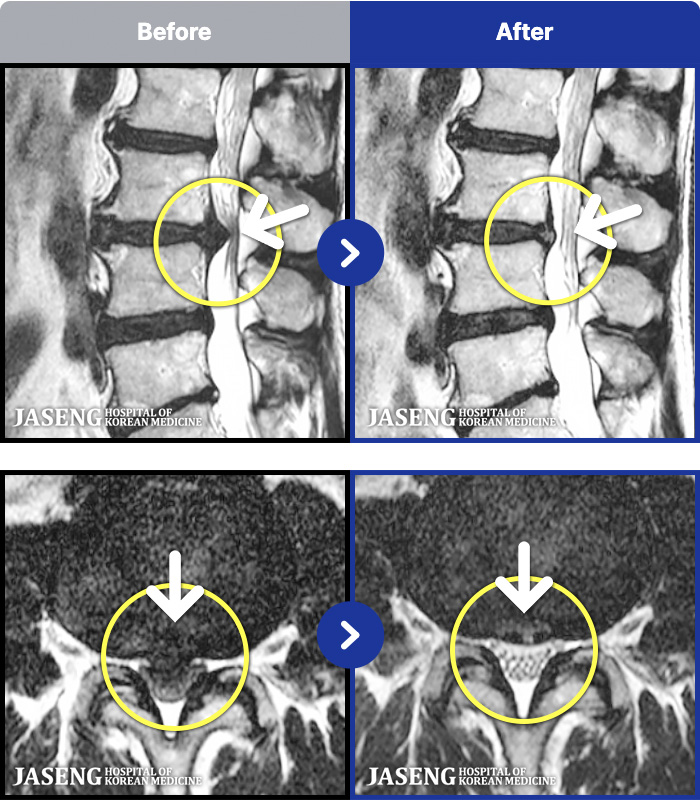

191 MRI ũ ʸ Ȯϼ.

ȯںп Ǹ ǿ ԿǾ, ο ġ ۿ Ƿ ġḦ Ͻñ ٶϴ.